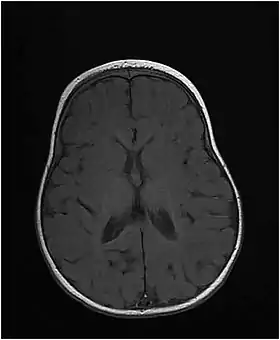

The disease starts at birth or in early infancy and presents with microcephaly, short stature, and developmental delay. Patients develop seizures that may be hard to control. Brain imaging shows delayed myelination and hypomyelination.[2] Mutations of the MTHFS gene disrupt folate metabolism, which is very important for the proper development of the nervous system and myelination of nerve fibers.[2]